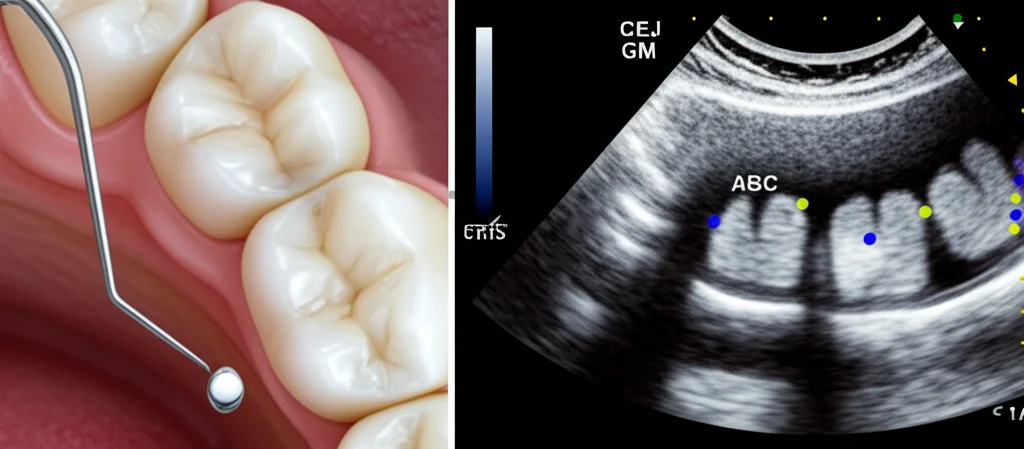

Ed è qui che entra in gioco l’ecografia. Sì, proprio quella che si usa per vedere i bambini nella pancia della mamma o per controllare i nostri organi interni! Negli ultimi anni, abbiamo iniziato a esplorare il suo potenziale anche in odontoiatria, in particolare per valutare la salute parodontale e peri-implantare. Perché? Semplice: l’ecografia è non invasiva, non usa radiazioni ionizzanti e ci permette di vedere benissimo sia i tessuti molli (le gengive) che quelli duri (l’osso), identificando punti di riferimento anatomici cruciali come:

- La cresta ossea alveolare (ABC – Alveolar Bone Crest)

- La giunzione cemento-smalto (CEJ – Cementoenamel Junction), un riferimento chiave

- Il margine gengivale (GM – Gingival Margin)

Da queste immagini, possiamo ricavare misure importantissime, come la recessione gengivale (quanto la gengiva si è ritirata) o la perdita ossea, con una precisione che può arrivare fino a 50 µm! Fantastico, vero? Studi precedenti avevano già dimostrato la validità dell’ecografia, ma spesso si limitavano ai denti anteriori a causa delle dimensioni dei trasduttori (le “sonde” ecografiche).

Prima di tutto, abbiamo confermato che il trasduttore “hockey-stick” funziona davvero per raggiungere anche i denti posteriori. Poi, abbiamo analizzato le immagini ecografiche identificando i famosi punti di riferimento (ABC, CEJ, GM) e misurando le distanze tra loro. Abbiamo definito queste misure “ecografiche”:

- iGR (imaging-based Gingival Recession): distanza tra margine gengivale (GM) e giunzione cemento-smalto (CEJ). Può essere negativa se la gengiva copre la CEJ, positiva se c’è recessione.

- iABL (imaging-based Alveolar Bone Loss): distanza tra cresta ossea (ABC) e CEJ, per valutare la perdita ossea.

- iGH (imaging-based Gingival Height): distanza tra cresta ossea (ABC) e margine gengivale (GM).

- iGT (imaging-based Gingival Thickness): lo spessore della gengiva misurato a livello della CEJ.